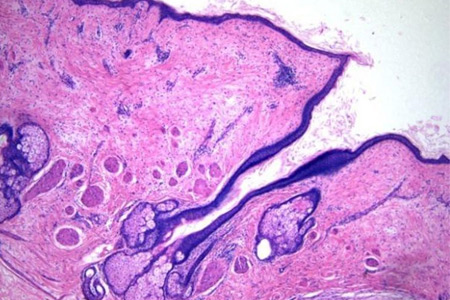

皮膚癌是一種發生在皮膚表面的惡性腫瘤,常見的類型包括基底細胞癌、鱗狀細胞癌和黑色素瘤等。雖然大多數皮膚癌在經過适當的治療後可以治愈,但有些癌症可能會導緻皮膚癌的複發。

基底細胞癌

基底細胞癌是最常見的皮膚癌類型之一,通常發生在老年人身上。這種癌症通常不會引起嚴重的健康問題,但有時會在治療後複發。基底細胞癌的複發通常是由于治療不徹底或腫瘤切除不完全所緻。

鱗狀細胞癌

鱗狀細胞癌是一種較爲嚴重的皮膚癌類型,通常會在治療後複發。這種癌症通常是由于長期慢性炎症或紫外線照射所緻。鱗狀細胞癌的複發通常是由于治療不徹底或腫瘤切除不完全所緻。